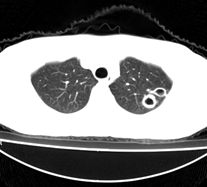

病人为一考上研究生的学生,健康体检发现。请踊跃发表意见。

左肺上叶见后段近侧胸壁见两个薄壁空洞影,洞内无液平,考虑肺囊肿,因为肺囊肿位于肺的外周,囊肿与支气管相通,囊壁薄,囊内无液性成分。以上使我的观点,原与各位交流

左肺上叶尖后段胸膜下可见两个类圆形薄壁空洞,内外壁较光滑,腔内为气体密度,支持结核性薄壁空洞。

我想应是肺囊肿,因为边界清晰,其内无液平面,周边没有卫星灶,还有临床也不支持肺结核

临床无症状,左上肺两枚厚壁空洞,内无气液平面,周围未见卫星灶,囊肿可能大,建议追问病史。请各位老师指正

左飞上叶尖后段两个含气的囊性肿块,边界清晰,其周围未见卫星病灶,考虑肺囊肿.不支持肺结核是因为未见卫星灶,临床未见体征.

左肺上叶后段见两个孤立圆形厚壁空洞,无液平及壁结节。周围清晰,无卫星灶。结合病史,如此大的病灶病人毫无感觉,另外周围如此清晰,应能排除结核空洞;肺囊肿壁应更薄,如合并感染可增厚,但周围应模糊。本人考虑:肺韦格肉芽肿。

左肺上叶后段见两个孤立圆形厚壁空洞,无液平及壁结节。周围清晰,无卫星灶。结合病史,如此的病灶病人毫无感觉.考虑1肺部感染[注意新隐球菌感染----中华放射学杂志---2006----第一期-----104页]。2肺囊肿。请指教!!!

左上叶尖后段可见两个中等壁厚空洞,腔内无液平,内外壁光整,局部轻度胸膜增厚,首虑结核。

考虑肺囊肿可能性大。不支持结核是因为周围肺野内未见明显卫星灶及纤维索条,不支持韦格氏肉芽肿是因为内壁及外壁均很光整,壁厚薄一致,而韦格氏肉芽肿洞壁厚薄多不均匀,内壁多不规则,其内可有形态不规则的内容物。

左肺尖后段的两个薄壁(纵隔窗)含气囊样病变,壁厚薄较均匀、光整、内无液气平形成、其邻近肺野见

少许渗出、未见卫星灶,其余肺野未见明显支气管播散灶(楼主虽然未上传全其他层面图片,但认为因正常而未上传)。

综合上述:考虑为肺囊肿合并感染,不支持结核空洞(虽然病变位于结核好发区,但认为这么明显的结核空洞应该有明显的肺内支气管播散灶)。